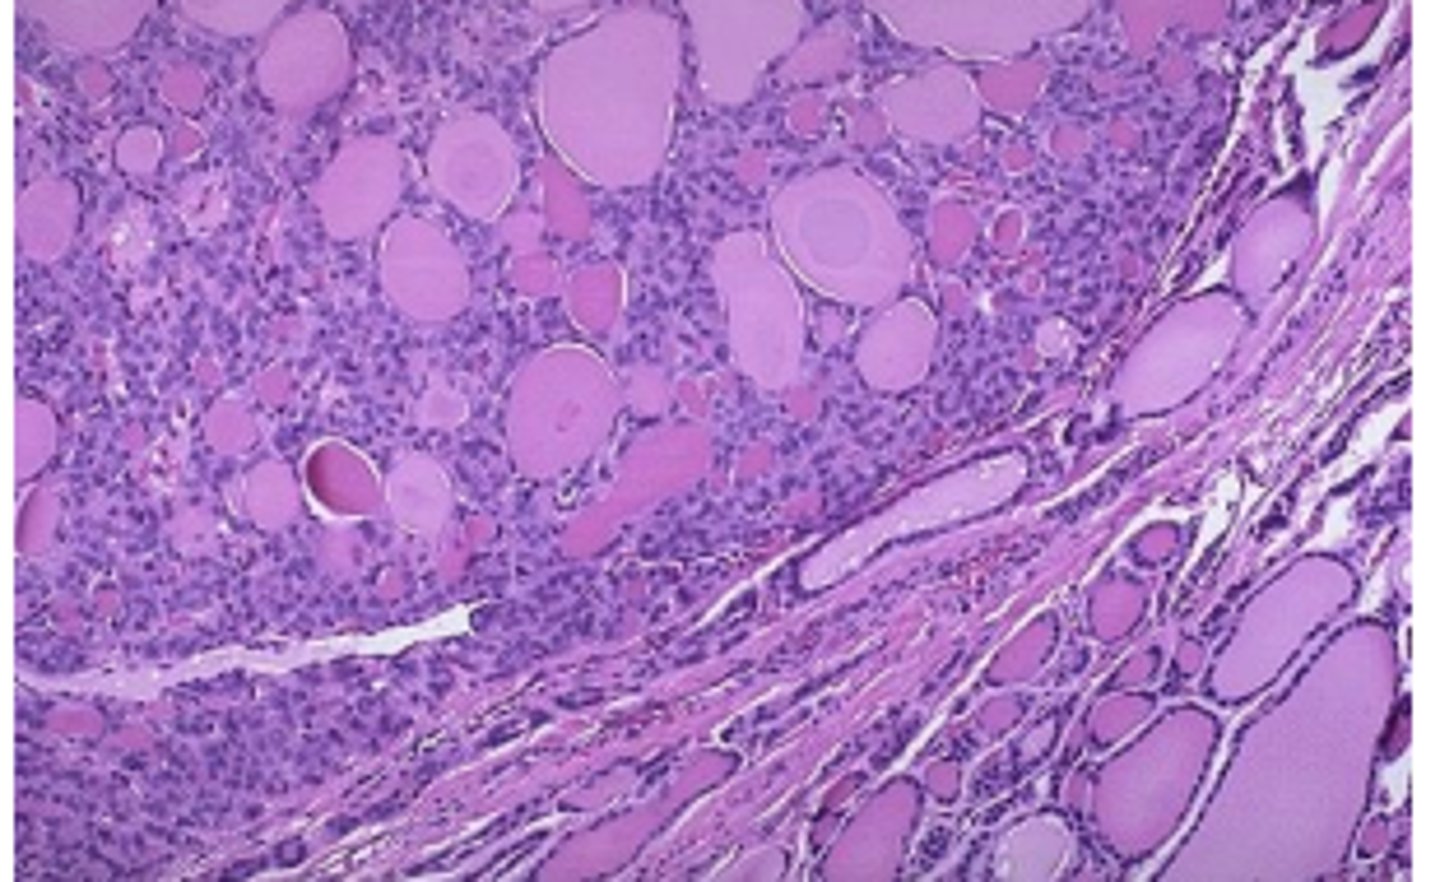

medullary thyroid carcinoma

neuroendocrine neoplasms derived form the parafollicular (C cells)

calcitonin

medullary thyroid carcinomas secrete

amyloid stains positively with calcitonin immunostains